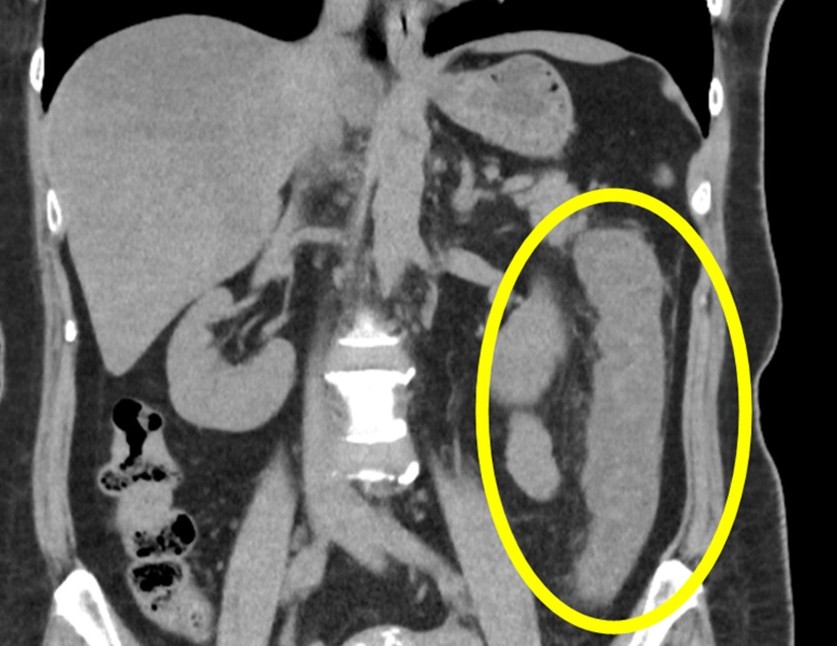

CT検査(コンピューター断層撮影)

- 腸の壁がむくんで厚くなっている様子が確認できます。

- 重症の虚血では、腸の壁の中にガスが貯留する「腸管気腫(pneumatosis coli)」や、腹腔内の液体貯留が見られることもあります。

- 造影剤を使用して腸の血管の状態や血流不全の有無を評価することもあります。

- 他の腹痛の原因(虫垂炎、憩室炎、腸閉塞など)を除外するためにも有用です。